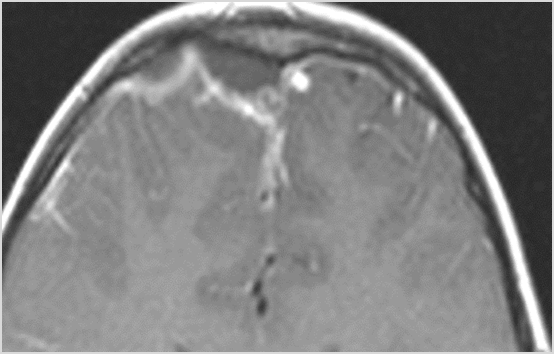

45-year-old immune compromised patient in the bone marrow transplant unit with neutropenic fever and frontal headaches with likely sinusitis possibly with possible orbital, intracranial or other complications such as cavernous sinus thrombosis.Exam

There is evidence of thrombus, thrombophlebitis or other occlusive or inflammatory process of the cortical veins, sphenoparietal sinus or sagittal sinus. |

No | NA |

Findings are consistent with the clinical diagnosis of uncomplicated acute or subacute sinusitis with probable acute frontal sinus air/fluid level.

No recommendations except to raise the awareness to monitor for clinical indications of worsening possible acute frontal sinusitis

Urgent (Action Necessary in a few hours)